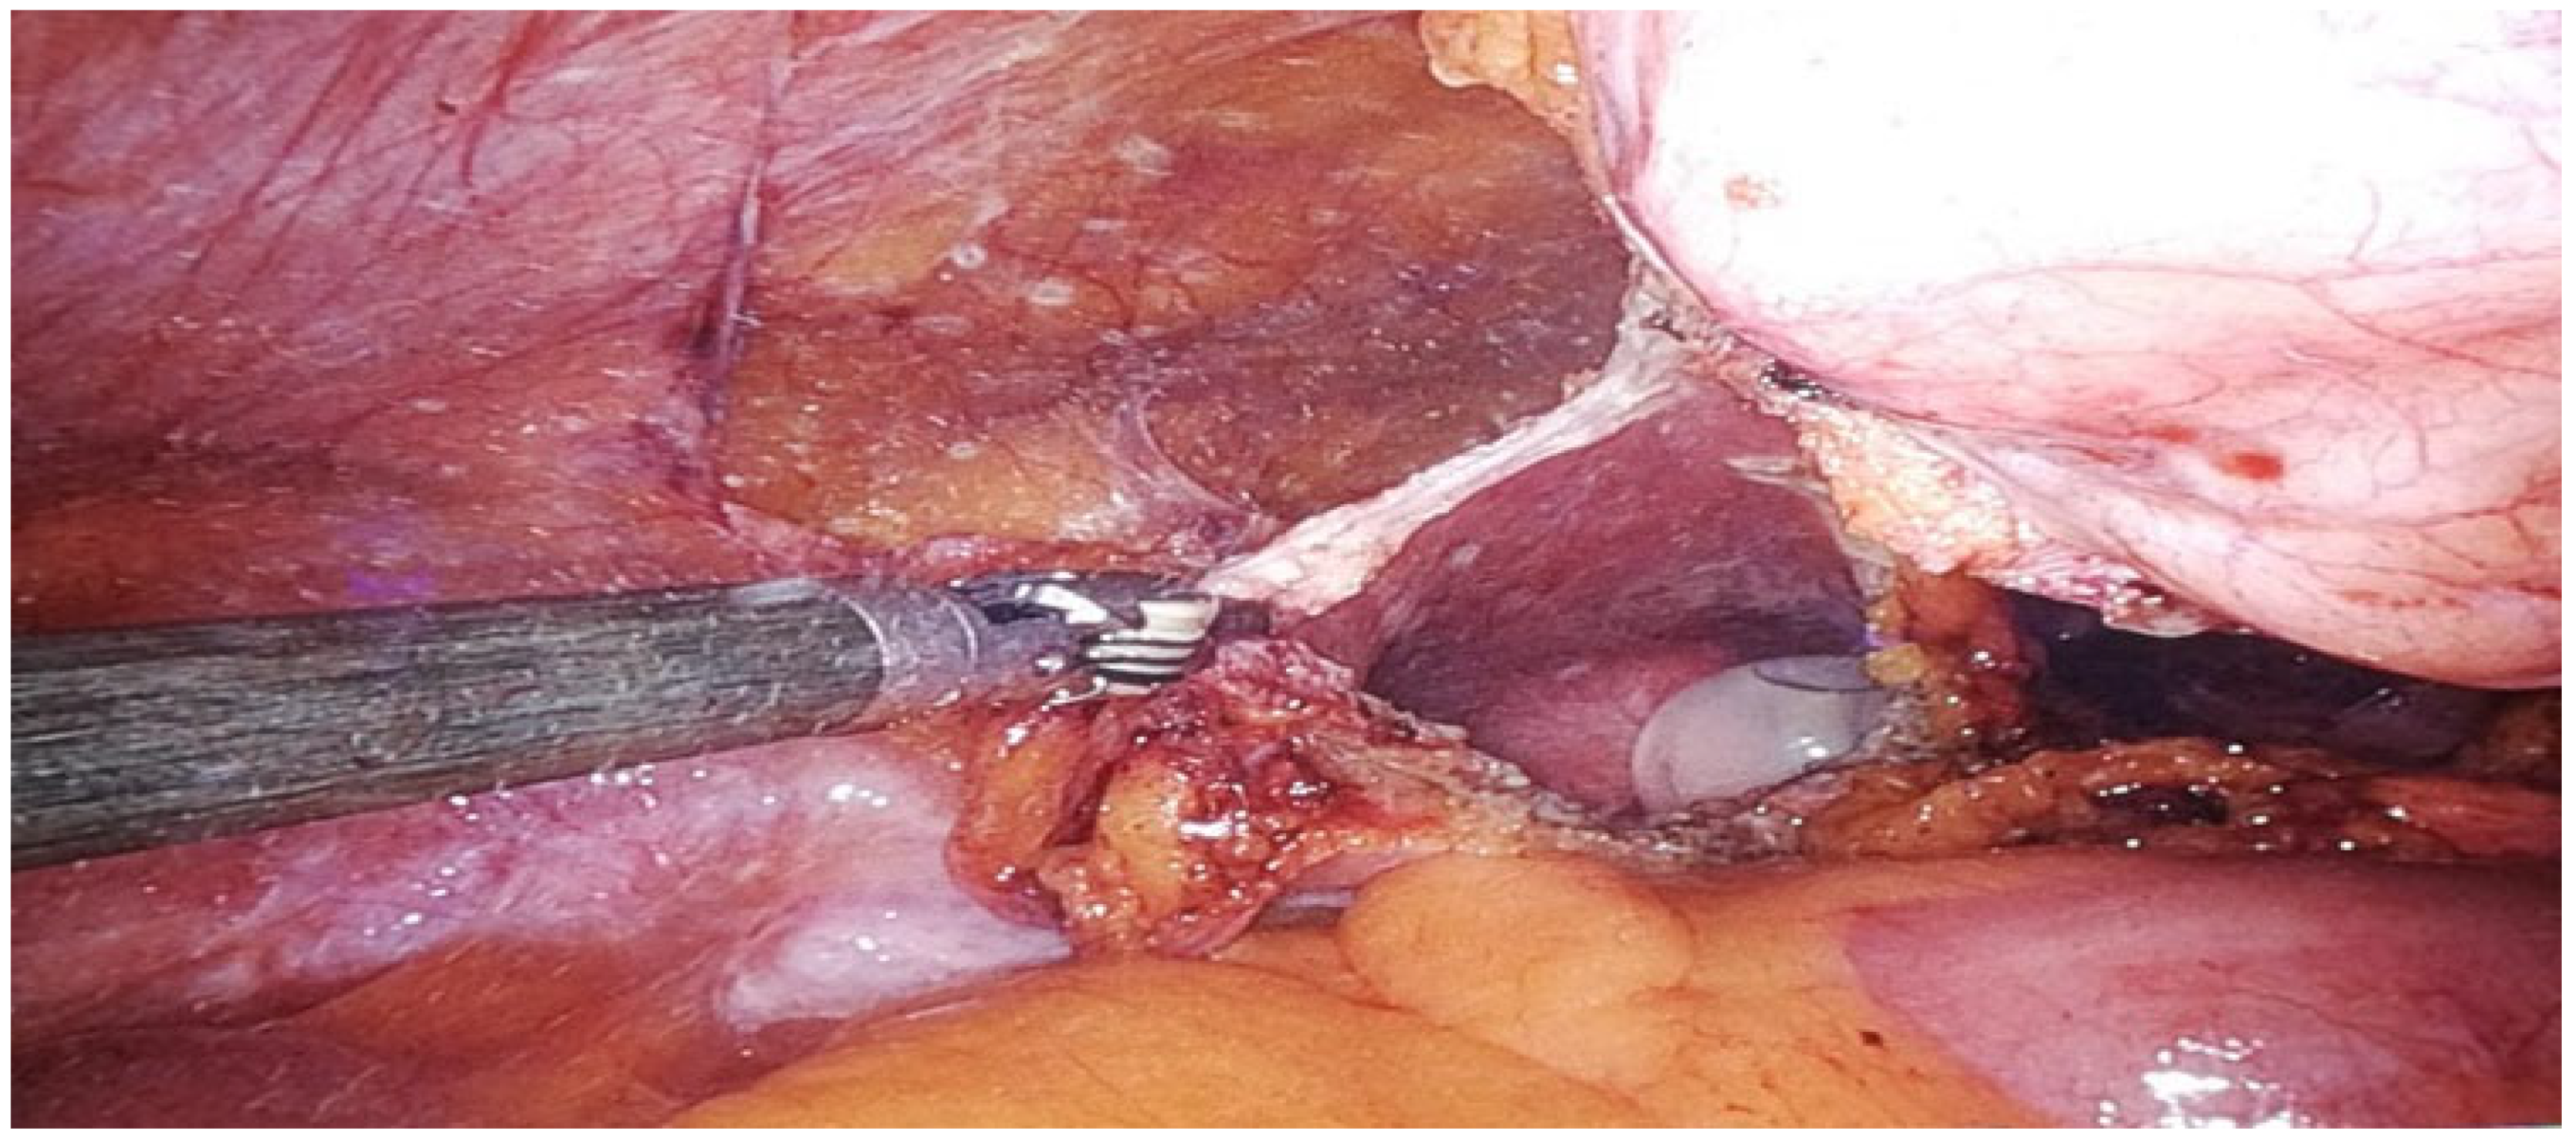

| Drobot RB 15 December 2022 | Multidisciplinary Hospital in Warsaw-Miedzylesie (Poland) | 9.9 ⟶ 8.4 | Suspected urachal tumor on CT (contrast-enhanced tissue mass) | Chronic suprapubic pain | CT | Normal | No | No | No | No | No | II Clavien Dindo: red blood cell concentrate transfusion | 7 (3 postoperatively) | Tissue fragment measuring 13 × 5 cm, consisting of adipose tissue, and an adjacent cohesive element measuring 3 × 2 × 5 cm. The obfuscated material is not very legible. Urachus without tumor. | da Vinci X | 90 | 55 | 450 | Male | 44 | 20 | No | Not Applicable (N/A) | Yes | No evidence of pathology | No | N/A |

| Drobot RB 19 October 2023 | Multidisciplinary Hospital in Warsaw-Miedzylesie (Poland) | 9.5 ⟶ 8.4 | Urachal tumor Shelodon IIIA stage | Suprapubic pain, hematuria | CT | Tumor at the dome of the bladder | No | No | No | No | No | None | 5 (2 postoperatively) | Cystadenocarcinoma mucinosum lesion excised completely (R0). | da Vinci X | 85 | 50 | 150 | Male | 66 | 10 | Yes | Normal (cT0) | Yes | No evidence of recurrence (N0, M0) | No | N/A |

| Drobot RB 12 September 2024 | Multidisciplinary Hospital in Warsaw-Miedzylesie (Poland) | 9.4 ⟶ 9.1 | Suspected urachal tumor on CT | Microscopic hematuria | CT | Tumor at the dome of the bladder | No | No | No | No | No | None | 7 (3 postoperatively) | The examined material includes samples of the patent urachus with focal, moderately abundant chronic inflammatory infiltrates; no neoplastic tissue is observed | da Vinci X | 81 | 68 | 50 | Male | 48 | 2 | No | N/A | No | N/A | No | N/A |